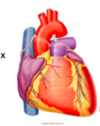

Describe the hearts shape from the anterior view

Apex of the heart hangs the most inferior and to the left, running laterally to the right is the diaphragmatic surface. The appendage (purple) is the right atrium.

Describe the shape of the heart from the posterior view

The base of the heart can be seen from the posterior view and is formed by the meft atrium NOT the diaphragmatic surface.

Below the base of the heart is the diaphragmatic surface formed by the let ventricle.

(can also see the R and L pulmonary arteries, SVC and IVC entering the Right atrium and the arch of the aorta.

The heart is a _________ structure that rotates to the _____ during development.

The heart is a midline structure that rotates to the left during development.